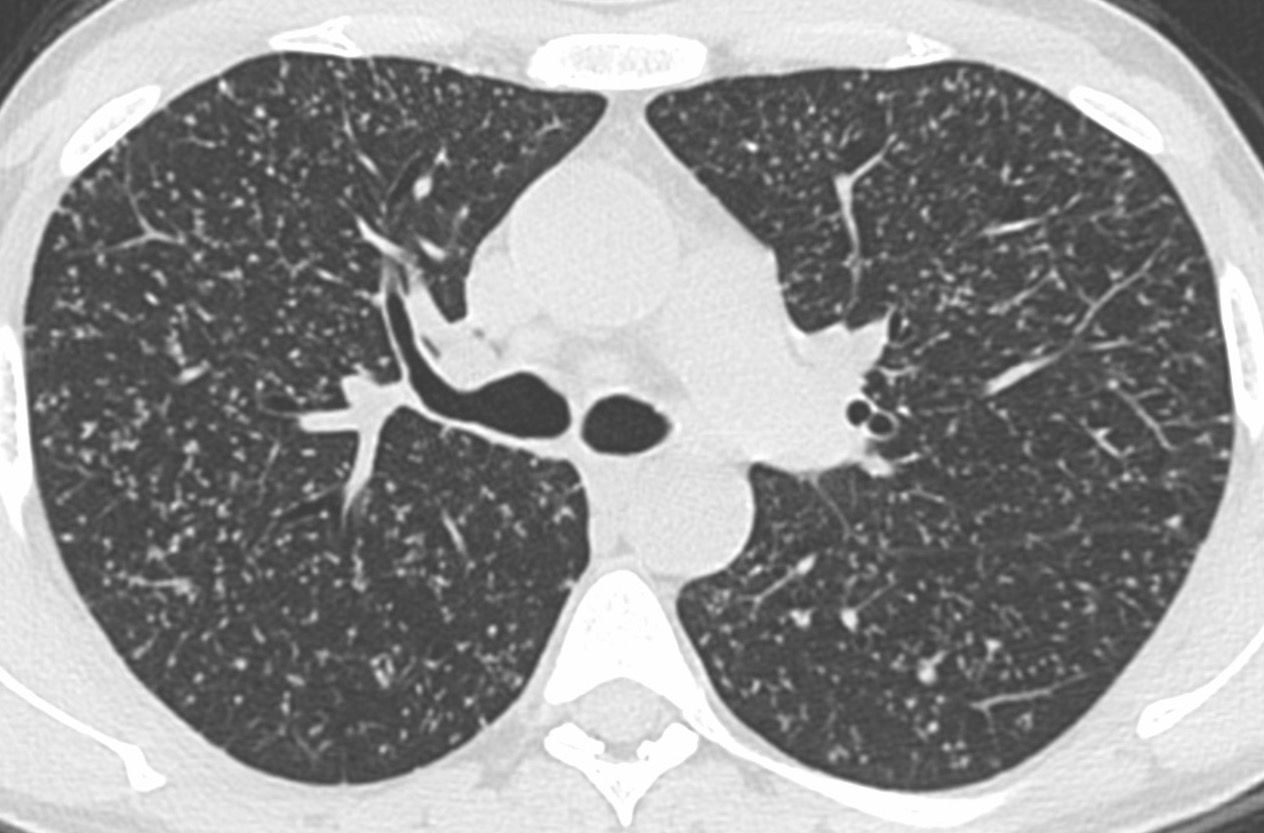

Case 84: Same Sized Small Lung Nodules

30-years old with cough and fever

This is a 30-years old who presented with cough and fever.

- Miliary TB

- Metastases

- Tree-in-bud - infectious bronchiolitis TB

- Tropical eosinophilia